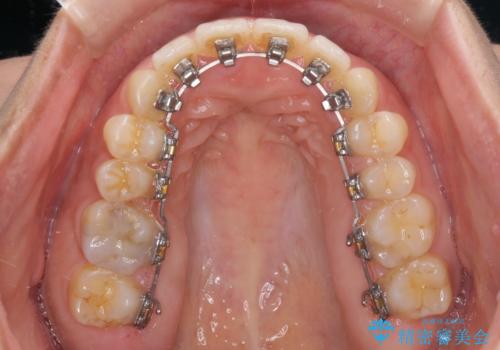

- フルリンガル

- 1年10ヶ月

- 10-30回

下顎が左側にずれているため、裏側矯正ということもあり咬み合わせを整えるのに時間がかかってしまいました。